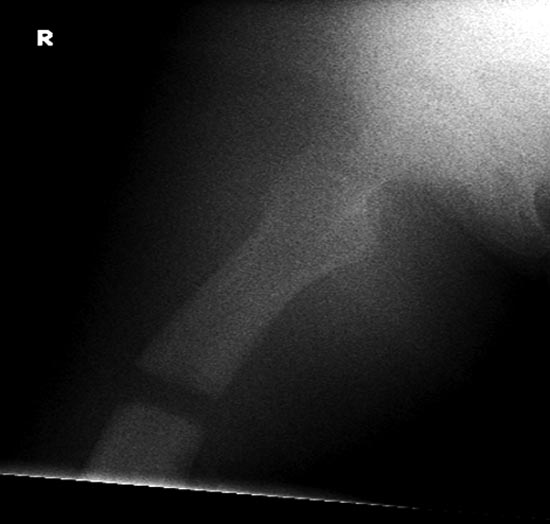

На 25 день с момента травмы операция на Jackson table с боковым обширным доступом. Удаление стержней с местной обработкой. В тазобедренном суставе удаление головки, на дне вертлужной впадины полная отслойка хряща. Вертлужный компонент с одним винтом и короткая ножка - Fitmore press fit stem. На второй день однократно доза радиации для профилактики гетеретопической оссификации. Послеоперационный период без температуры. Выписана. Нагрузку разрешили на левой стороне, а полная в 3 мес. Здесь снимки при амбулаторном наблюдении: послеоперационно, 2 мес, 3 мес и 6 мес. Нагрузка полная, отсутствует хромота, и нет жалоб.